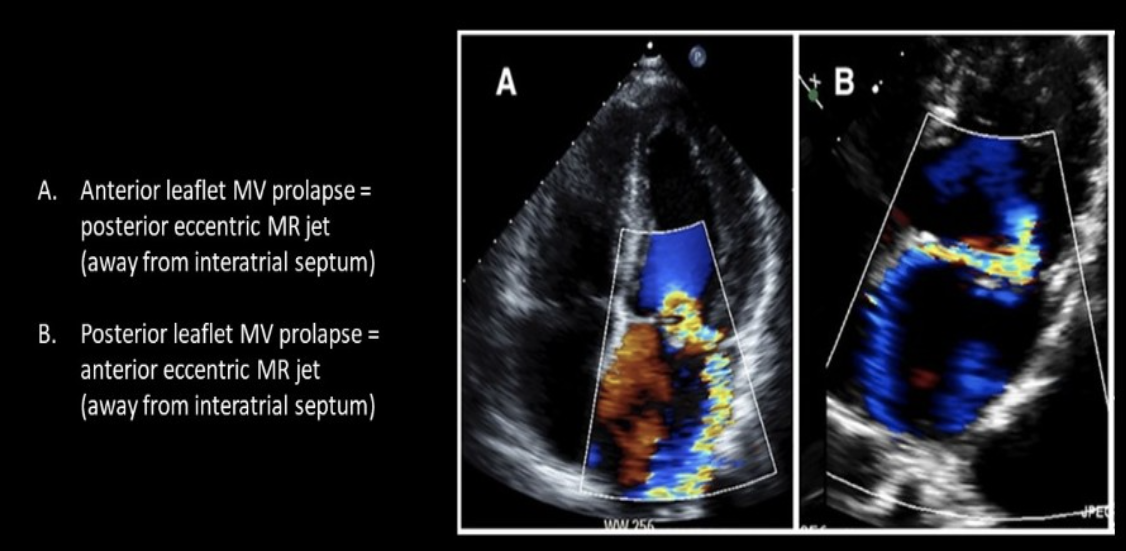

Tendency of fluid jet to flow adjacent to a convex surface

Coanda effect

Doppler waveform most suggestive of?

MVP